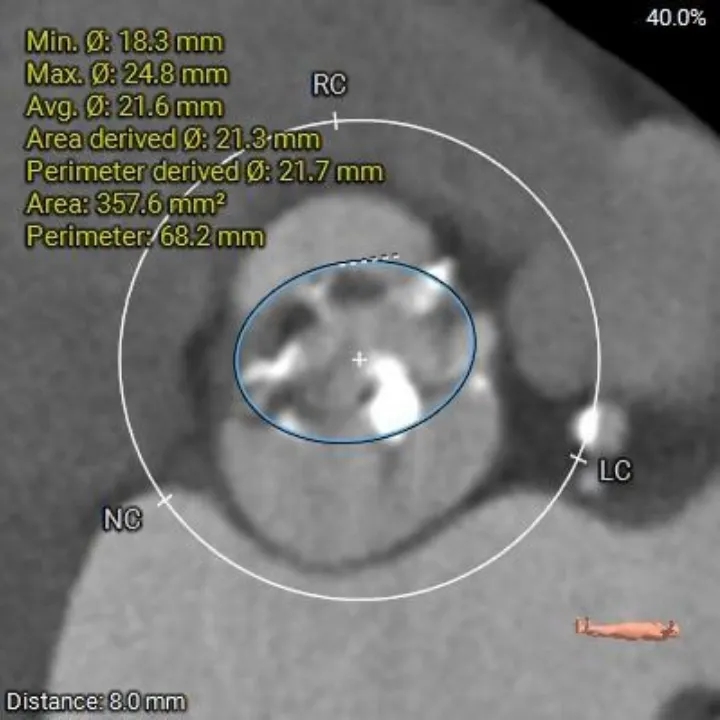

主动脉根部测量

Annulus

23.8mm

LVOT

22.4mm

横列式Type0型二叶瓣,瓣环内径23.8mm

瓣上结构测量

瓣上2mm

21.6mm

瓣上4mm

21.9 mm

瓣上6mm

21.7 mm

瓣上8mm

21.7mm

瓣上10mm

21.1mm

瓣下2mm

22.2mm

瓣上限制较重,可见明显左窦瓣叶偏心钙化,限制最重区域为瓣上4-8mm。